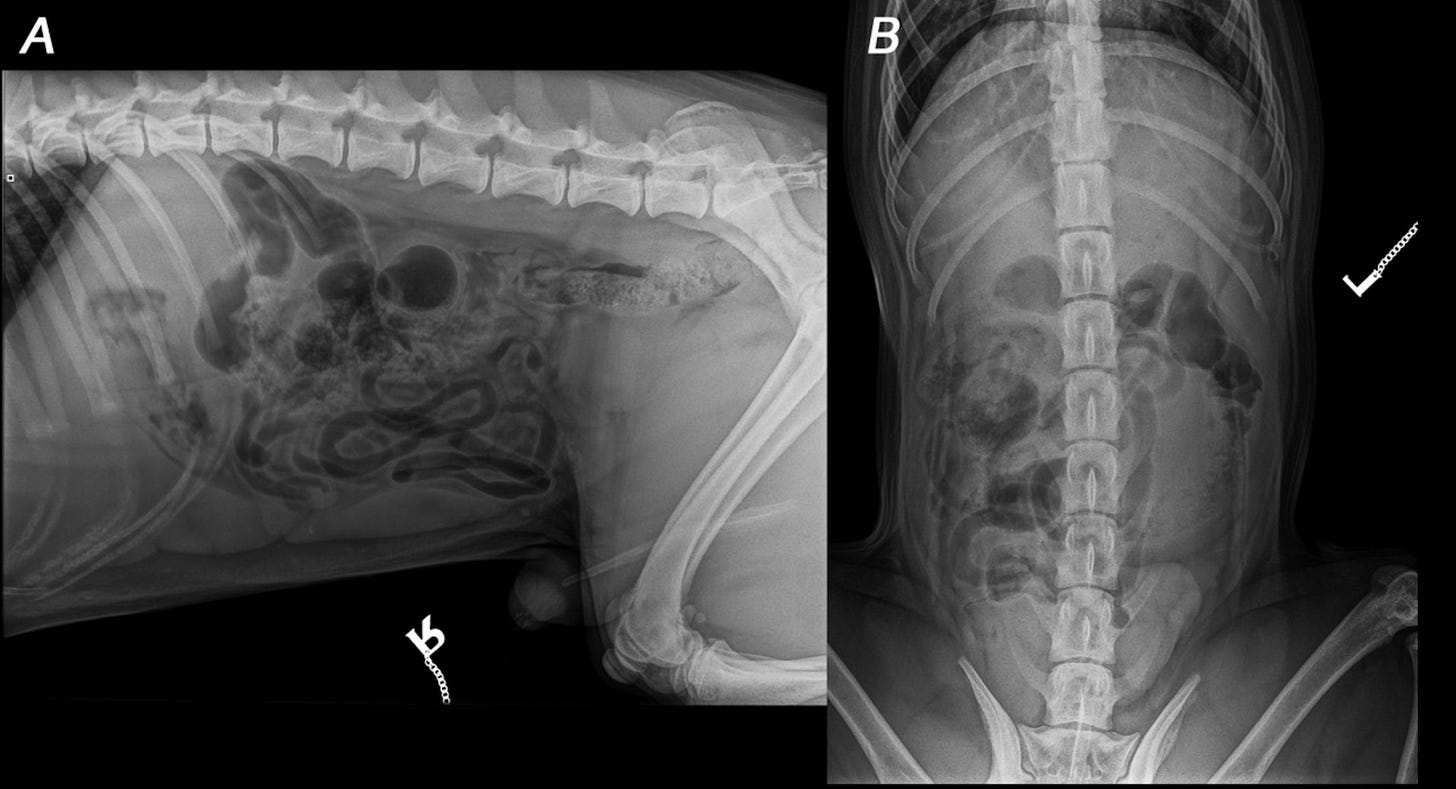

In total, 53 cases were included and submitted to the six AI services. Vetology rejected 11 cases (over 20%), all other services evaluated every case. At the simplest “case” level (binary call of normal or abnormal), sensitivity ranged from 71-90% (meaning 10-29% false negatives), and specificity and negative predictive values (NPV) were quite low for all. These results are summarized in Table 2:

As you can probably imagine based on the “meh” (at best) topline numbers for just calling normal vs abnormal, the results for specific diagnoses were quite a bit worse. Sensitivity ranged from 28% to 78% for specific conditions, and was <50% for 5/6 companies. Perhaps unsurprisingly, the service with the highest sensitivity (X Caliber) also had the highest rate of false positive errors. You can see an example of this in the first half of Figure 2 below:

The results got truly scary when they zeroed in on specific urgent, life-threatening conditions like an intestinal obstruction (which requires immediate surgery). Sensitivity was poor across companies (23-69%), and none had an overall accuracy score in the 90s. See Table 4: